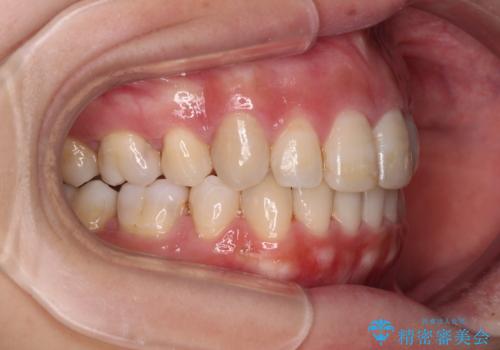

突出した口元が気になる ハーフリンガル装置による抜歯矯正

- 口元の突出感を気にして来院された患者様です。

通常では上下左右の第一小臼歯4本を抜歯しますが、下顎が左側にシフトしていたため、下顎左側のみ第二小臼歯を抜歯し、正中を合わせながら口元を下げる治療計画としました。

ハーフリンガルは、通常では表側のワイヤー矯正よりも治療期間がかかります。特に今回のように下顎左側をイレギュラーの第二小臼歯抜歯としたため、さらに時間がかかることが予想されました。

実際に治療をおこなってみると、2年を切る短期間で治療を終えることができました。